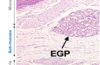

מה בסלייד?

קיבה